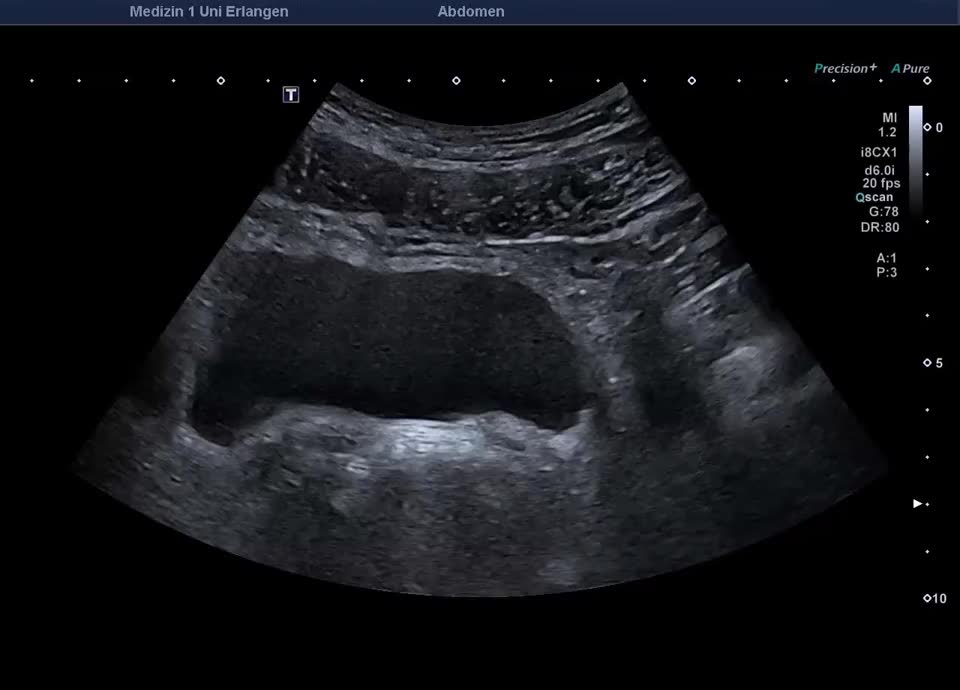

55-jähriger Patient mit abdominellen Beschwerden. Sonographisch stellt sich die linke Niere mit einem altersentsprechenden Parenchymsaum und regelrechter Mark-/Rindendifferenzierung dar. Das Nierenbeckenkelchsystem ist nicht erweitert. Distal im Bereich des Harnblasenostiums zeigt sich ein Konkrement von ca. 6 mm im Ureter, begleitet von positivem Twinkling-Artefakt im Farbdoppler. Der Ureter ist diskret erweitert, proximal bis 10mm. Sonographischer Befund vereinbar mit einer Ureterolithiasis im distalen linken Ureter (Ostium Harnblasenboden).